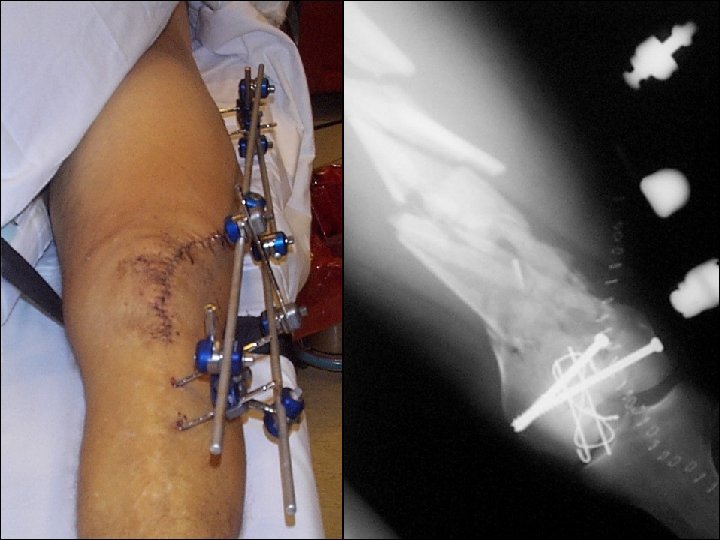

32 -year-old male, motor vehicle accident, open grade II

Reduction and fixation? 1. Closed indirect reduction and IM nailing 2. Closed indirect reduction and plate fixation 3. Closed indirect reduction and external fixation 4. Open direct reduction and plate fixation

Wound healed—what now? 1. Continue with external fixation 2. Closed reduction and retrograde nail 3. Closed reduction and locked plate 4. Open reduction and plating